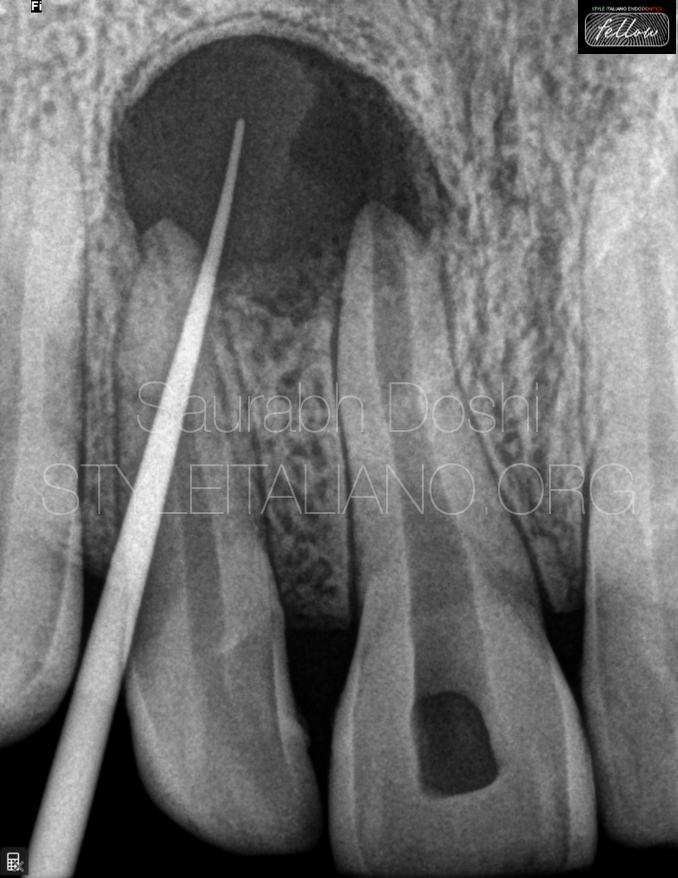

what is a real image

when structure lies between receptor and moving rotation center